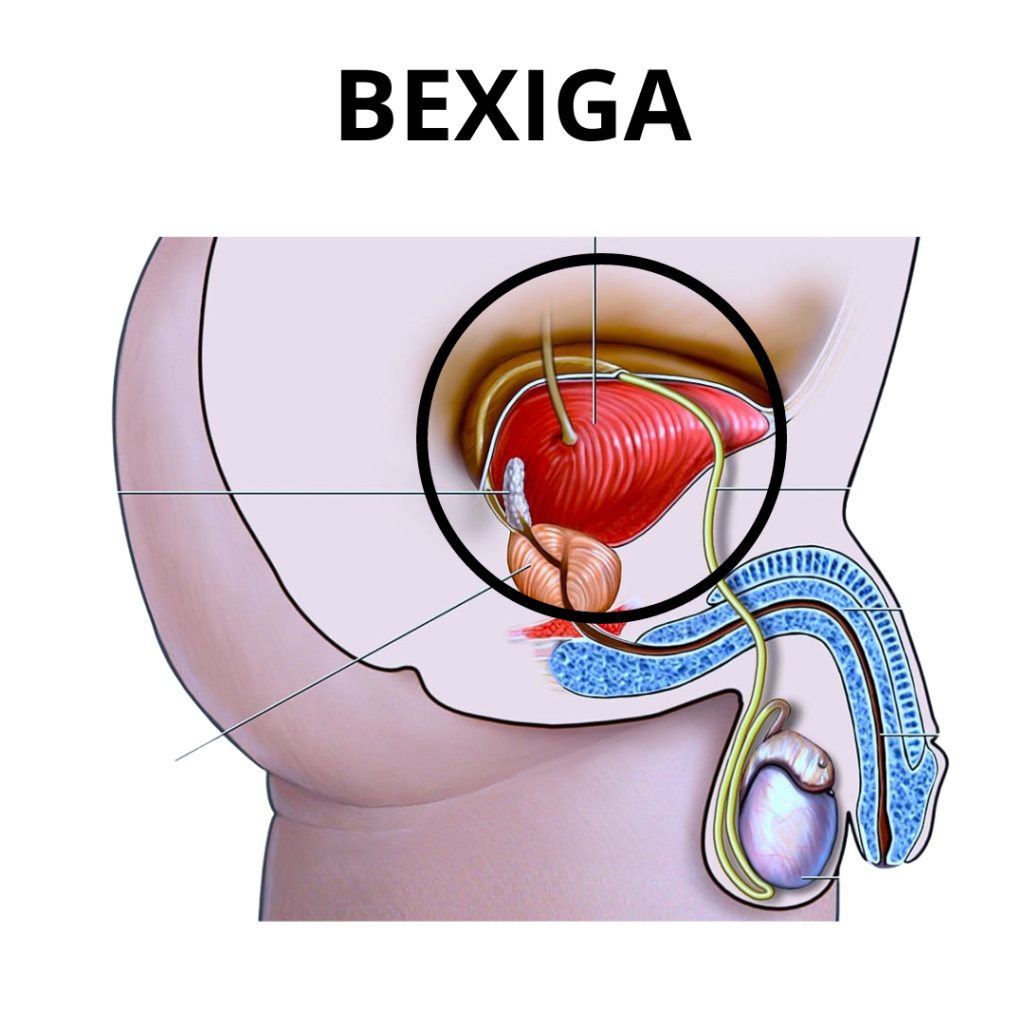

DOENÇAS DA BEXIGA

Tumores benignos e malignos

Bexiga Hiperativa

Incontinência urinária

E outras doenças saiba mais no botão CONSULTA abaixo.